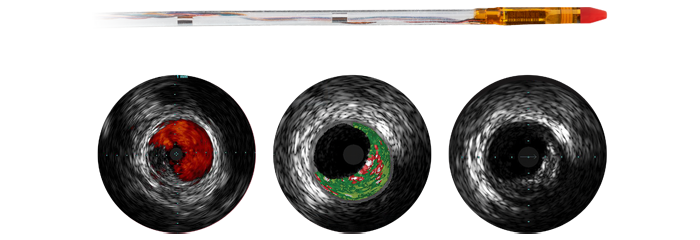

Eagle Eye Platinum

Digital IVUS catheter

The Eagle Eye Platinum digital IVUS catheter is the #1 choice of physicians for intravascular imaging (in the US). *As a unique plug-and-play intravascular imaging catheter it is designed for ease of use and deliverability. Features include a soft tapered tip, GlyDx hydrophilic coating for increased lubricity, a long, rapid exchange lumen for improved pushability, three radiopaque markers, and compatibility with IntraSight and SyncVision for co-registration with angiography.

Instant Wave-Free Ratio — iFR

The leading hyperemia-free physiologic index for measuring pressure in diagnostic and interventional procedures, which can improve outcomes, save time, and reduce patient discomfort. iFR is measured using the world's first solid core pressure guide wire, OmniWire, with values co-registered* directly on the angiogram. This advanced physiologic guidance helps identify precisely which parts of a vessel are causing ischemia, to help determine treatment strategy.

*Available with IntraSight 7 and SyncVisionYou are about to visit a Philips global content page

Eagle Eye Platinum

The Eagle Eye Platinum digital IVUS catheter is the #1 choice of physicians for intravascular imaging (in the US).* As a unique plug-and-play intravascular imaging catheter it is designed for ease of use and deliverability. Features include a soft tapered tip, GlyDx hydrophilic coating for increased lubricity, a long, rapid exchange lumen for improved pushability, three radiopaque markers, and compatibility with SyncVision for co-registration with angiography.